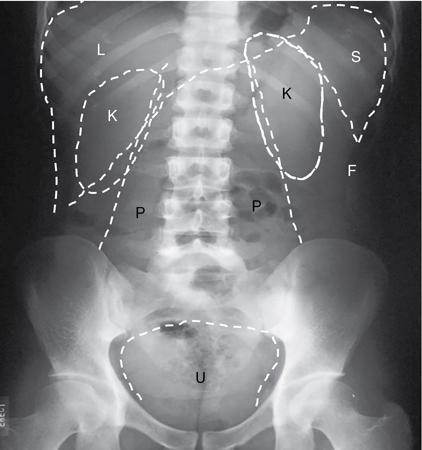

UNDERSTANDING THE ADULT ABDOMINAL RADIOGRAPH: TECHNIQUES AND INTERPRETATION Tanvi Modi Radiography of the abdomen is a common practice for the evaluation of abdominal organs. The anatomy and pathology of digestive, hepatobiliary and genitourinary systems can be assessed using radiographs, either as a stand-alone practice or as a primary imaging modality followed by contrast studies, ultrasound or cross-sectional imaging. In addition, abnormalities of the musculoskeletal or integumentary system can also be deduced on the basis of abdominal radiographs. This chapter intends to give an overview on the techniques and positioning in abdominal radiography as well as interpretation of normal and abnormal features. While superior imaging modalities such as ultrasound, computed tomography (CT), magnetic resonance imaging, capsule endoscopy and the likes have taken over abdominal imaging by and large, radiography still holds a pivotal role in certain situations and conditions, such as: The standard abdominal radiograph is taken in supine position and anteroposterior projection. This is also popularly known as the KUB (kidneys-ureters-bladder) radiograph. Previously, supine as well as erect radiographs were performed in all patients; however, this is not commonly done due to high-radiation dose. For all indications of abdominal radiography, including acute abdomen, supine radiographs are sufficient in terms of radiographic diagnosis, with the exception of perforation for which an erect chest or lateral decubitus radiograph can be performed if there is clinical suspicion. Patient should lie supine on the imaging table with median sagittal plane at right angles to the table and coincident with the midline of the table (Fig. 7.1.1.1). The body is divided into equal right and left halves by the median sagittal which passes through the sagittal suture of the skull. Pelvis should be adjusted so that the anterior superior iliac spines are equidistant from the table top. Gonadal shields, in the case of male patients, should be placed with the upper edge of the shield at the level of pubic symphysis. Although rarely used for female patients, these should be positioned between the anterior superior iliac spines and the pubic symphysis. The centre point of the image receptor should be approximately located at a point 1 cm below the line joining the iliac crests. The X-ray beam should be in a vertical direction, perpendicular to the table top and image receptor at the centre point. Collimation should be such that the soft tissue and subcutaneous region along lateral aspects of the abdominal cavity should be covered within the image. Also, the superior extent involving diaphragm and inferior extent involving the inferior pubic rami is important to look for any lower chest pathologies or any inguinal hernia. 35 × 43 cm (14 × 17 inches) in portrait orientation. On an average, abdominal radiograph exposes a patient to a dose of approximately 1.5 mSv, which is equivalent to 75 chest radiographs or 1/6th dose of a standard CT of the abdomen. The entrance skin dose is approximated to be 4 mGy. At such an effective dose, the additional lifetime risk of fatal cancer is 1 in 30,000. The exposure time is kept short. Patient is asked to exhale completely and hold their breath, with exposure taken at this point of full expiration to ensure imaging of abdominal organs in their natural positions. Modifications of this technique can be made depending on patient habitus and clinical condition. Kilovoltage peak (kVp) should be set to allow adequate visualization of abdominal soft tissue structures as well as semiopaque renal and biliary calculi. Average kVp is set at 70–85 kV. 102 cm (40 inches) Grids are commonly used to reduce scatter radiation. Placement of side marker on the image receptor at the time of radiographic exposure is essential. Bowel pattern depiction should be such that there is minimal lack of sharpness. Standard guidelines for abdominal radiography dictate that the radiograph should extend from the diaphragm up to the level of inferior pubic rami and must include the lateral abdominal wall musculature. The abdomen is divided into four quadrants on the basis of two perpendicular lines (Fig. 7.1.1.7). The vertical line passes through the mid sagittal plane and crosses the umbilicus and symphysis pubis. The horizontal line is a transverse line across the umbilicus at 90 degrees to the vertical line and is situated at the level of L4–L5 intervertebral disc. The quadrants are as follows: Another division system is dividing the abdominopelvic cavity into nine regions using two vertical and two horizontal planes (Fig. 7.1.1.8). The vertical planes, also known as the right and left lateral planes, are parallel to the midsagittal plane between midline and anterosuperior iliac spines on either side. Of the two horizontal planes, the upper transpyloric plane is at the level of lower border of L1 and the lower transtubercular plane is at the level of L5. The nine regions are: On a standard radiograph, the exposure should be such that the stomach, bowel loops, outlines of liver, spleen, kidneys, psoas muscles should be well identified. Also, lumbar transverse processes should be seen. Arch of the pubic symphysis should be visible to evaluate bladder region. A well-centred film without rotation will demonstrate bilaterally symmetrical lower ribs, iliac wings, ischial spines and obturator foramina. Different structures seen on an abdominal radiograph can be classified into five basic densities: Identification of different structures depends on the relative degree of contrast between their densities. The demarcation is clearer in chest and is diminished in abdomen due to relative similar soft tissue density of various structures. On a normal radiograph, relatively large amounts of gas in stomach and colon with minimal small bowel gas can be seen. Further, colonic gas can vary from negligible to extensive, mimicking obstruction pattern; however, usually the gas is enough to delineate colonic haustral pattern. Faecal matter gives a mottled appearance to colonic gas. Short-air fluid levels on an erect radiograph may be seen even in normal cases. The normal appearance of small bowel loops on an abdominal radiograph follows the rule of threes: Stomach is seen in the left upper quadrant and is visualized when distended with air. It is commonly seen extending from T11 to L2 level. Common feature identifying the stomach is the fundal gas which is usually seen as an air fluid level within the gastric lumen. Small bowel loops are distributed to the centre of the abdominal cavity and large bowel loops are peripheral. Duodenum is predominantly situated in right upper quadrant. It extends to left upper quadrant in the region of duodenojejunal flexure. Jejunum occupies the left upper and lower quadrants and is easily identified due to the presence of thick, numerous, closely spaced valvulae conniventes (Fig. 7.1.1.9A). The ileum occupies both lower quadrants and extends into right upper quadrant. Ileum has few and less prominent valvulae as compared to jejunum (Fig. 7.1.1.9B). Ascending and descending colon are retroperitoneal and have relatively fixed positions along lateral aspect of the abdominal cavity on either side. Transverse and sigmoid colon, on the other hand, may have a variable position due to their mobility along mesocolon and redundant pattern. These can be identified with confidence on account of haustrations and faecal matter (Fig. 7.1.1.10). Haustrations are usually well seen in ascending and transverse colon and poorly delineated beyond splenic flexure. Caecum is in the right lower quadrant, though it may be mobile or pulled up. Rectal gas is usually seen in the midline at the level of pelvis and its presence rules out large bowel obstruction. All these positions may vary due to anatomical conditions such as malrotation or pathological conditions, for example volvulus. Liver, spleen and renal outlines cannot be completely traced with precision due to the overlap by bowel loops. On a frontal projection, the liver appears as a triangular structure occupying right and left hypochondrium and epigastric region. Occasionally, the right lobe may be seen extending lower than the right renal shadow. This is a normal variant known as Reidel’s lobe. Gall bladder is situated in the posterior and inferior region of the liver and any pathology of the gall bladder should be looked for in this region. On a lateral radiograph, the gall bladder is anterior to the midcoronal plane. This helps in distinguishing gall bladder calculi from renal calculi, which will be more posteriorly situated. Spleen is seen in left upper quadrant/left hypochondrium, flushed to left lower ribs and left hemidiaphragm. Pancreas is present in the epigastric region (right and left upper quadrants) and is usually not identified in the absence of a pathology. The kidneys are bean-shaped retroperitoneal organs which are seen on either side of the vertebral column and lateral to psoas muscles. Due to the presence of liver on the right side, this kidney is slightly lower in position as compared to its contralateral counterpart. The visualization of kidneys on radiographs is facilitated by the surrounding fatty capsule. Kidneys lie between T11–12 and L2 level, with left kidney 1 cm higher than the right. Psoas muscle shadow can be normally seen along lateral aspect of lumbar spine bilaterally and is mildly concave (Fig. 7.1.1.11). Abdominal wall muscles are not routinely assessed on radiography; however, inclusion of lateral abdominal wall (muscles as well as subcutaneous plane) is a must while performing radiography. The flank stripe or the properitoneal fat stripe is a fat density linear concavity seen along lateral abdominal wall (Fig. 7.1.1.11). It is bound by the paracolic gutters and air-filled ascending and descending colon. All the solid organs in the abdomen are identified due to the fat density outlining them. Distortion of these fat lines helps in identifying organomegaly or focal mass lesions. The dome of urinary bladder is outlined by fat, which aids in differentiating its density from other soft tissue structures of the pelvis. Not all calcifications seen on abdominal radiograph are abnormal. Some may depict age-related changes such as vascular calcifications involving abdominal aorta, pelvic vessels, splenic artery in the region of left upper quadrant. Within the pelvis, phleboliths may be seen and mistaken for urinary calculi. Assessment of lumbosacral spine, iliac bones and femoral heads can be made on the basis of plain radiography. Degenerative changes may be commonly seen. Lower ribs can also be evaluated for pathologies. Dilated small bowel loops with rounded soft tissue density in midline over umbilical region suggests obstruction secondary to umbilical hernia. Pneumoperitoneum must be looked for in all cases of acute abdomen. While erect chest and left lateral decubitus radiographs can detect even 1 mL of free air, there are multiple signs on supine radiograph to suggest this diagnosis, for example Rigler’s sign, falciform ligament sign, football sign (Figs. 7.1.1.24 and 7.1.1.25). Retroperitoneal perforation may demonstrate air outlining psoas muscles and retroperitoneal organs. Small amount of free air may persist in the abdominal cavity up to 3 weeks after surgery, although it usually resolves within a week. Clinical history is important in such cases. Air foci within the bowel wall may represent bowel ischaemia/strangulation. Linear gas patterns in right hypochondrium may be due to two causes, that is pneumobilia and pneumoporta. The former can be seen normally postbiliary surgery, sphincterotomy, ERCP or in the case of abnormal fistulous communication between bowel and biliary tree (Fig. 7.1.1.26A). Pneumoporta (Fig. 7.1.1.26B) is a red flag and warrants further investigation to look for conditions such as mesenteric ischaemia and toxic megacolon. Pneumobilia is more centrally located whereas air shadows in pneumoporta are seen reaching up to periphery of liver. Air foci over renal shadows (Fig. 7.1.1.27), gall bladder or pancreas, in the absence of recent procedural history, suggest fulminant infection and mandate urgent intervention. Central midline calcific foci between T9 and T12 vertebrae can be attributed to calcific pancreatitis (Fig. 7.1.1.28). In the left upper quadrant, areas of calcification seen involving a shrunken spleen may be seen in autosplenectomy. In right upper quadrant, calcified gall stones may be seen. These tend to be small, multiple, uniformly circumscribed and ring-like in appearance with central translucency (Fig. 7.1.1.29A). Mercedes Benz sign, a triradiate pattern of gas lucency, is associated with gallstones. In contrast, renal calculi are more commonly solitary, irregular, of homogenous density, conform to renal calyceal or pelvic outline (Fig. 7.1.1.29B) and are sometimes of staghorn configuration. On lateral view, the gall stones are more anteriorly located as compared to renal calculi, which may be partly superimposed on lumbar vertebrae. Ureteric calculi tend to overlap bony structures such as lumbar transverse processes (Fig. 7.1.1.29B) or sacroiliac joints. Extensive or patchy, curvilinear calcification of gall bladder wall is known as porcelain gall bladder which is often associated with malignant transformation. Calcification involving adrenal glands may be secondary to infection or haematoma, or a congenital condition known as Wolman’s disease where there is bilateral involvement. Discontinuous discrete midline tram track calcification in the abdomen may indicate atherosclerotic changes in abdominal aorta and branch vessels. However, when the calcification is in a globular pattern and seen below the level of L2 vertebra, aortic aneurysm should be suspected (Fig. 7.1.1.30). Appendicoliths, though not commonly seen, may sometimes be detected in right iliac region. Pelvic calcifications: vesical calculi, distal ureteric or vesicoureteric junction calculi, calcified fibroids, ovarian dermoid with tooth-like calcifications (Fig. 7.1.1.31) may be the cause of abdominal pain and should be diligently looked for. Vesical calculi are usually more large and central in location whereas calcification due to fibroids may be more lateral. Schistosomiasis is another cause of bladder wall calcification, as is calcification of bladder tumours. Phleboliths tend to be bilaterally symmetrical, with a lucent centre unlike ureteric calculi. While it is believed that phleboliths are located below the level of ischial spines and ureteric calculi above, this is not always true and should be confirmed with CT. Fluid may collect adjacent to properitoneal fat line, forming a linear soft tissue density separating the fat line from the ascending or descending colon. Hellmer’s sign demonstrates medial displacement of lateral edge of liver (hepatic angle), due to fluid collection or ascites. Gross ascites may appear as generalized abdominal haziness or diffuse increased density of pelvis. Abscesses can involve any solid organ and in such cases may be difficult to demonstrate on plain radiography alone. Enlargement of organ or faint gas densities within can be suggestive of the same. In the case of peritoneal abscess, mottled density due to air, fluid and necrotic contents point towards this diagnosis, especially in right iliac fossa in association with appendicitis. Retroperitoneal abscess, similar to any retroperitoneal mass, may cause displacement of retroperitoneal structures (Fig. 7.1.1.32). Subdiaphragmatic abscesses may show concomitant ipsilateral pleural effusion (Fig. 7.1.1.33). These should be differentiated from Chilaiditi syndrome. Fluid and soft tissue lesions present with the same density on radiographs. While it is difficult to characterize the lesion and organ of origin, clues for the same can be provided by organomegaly (Fig. 7.1.1.34), distortion of fat surrounding solid organs, displacement of bowel loops or solid organs. For example, a retroperitoneal lesion may cause anterior or inferior displacement of kidney, a pelvic mass may cause upward displacement of small bowel loops. Different densities such as fat or calcification may help in identifying organ of origin (e.g. fat and tooth densities seen in ovarian dermoid). Convexity of margins of psoas muscle on an abdominal radiograph can be due to haematoma, abscess or intramuscular tumour. Radiographs are performed for the initial diagnosis of foreign body in the abdomen including type, number of foreign bodies, location, size and shape (Fig. 7.1.1.35). Radiolucent foreign bodies such as wood, plastic, chicken bones will not be easily identified on radiography. Low kVp (65–70 kVp) can increase contrast and help identify these objects. In addition to an abdominal radiograph, chest radiography is also performed to exclude aspiration or oesophageal location of foreign body. Ingested or introduced foreign bodies may cause complications such as obstruction, perforation, fistula formation and sepsis. Hence, once their presence is confirmed, follow up radiography must be performed until they are eliminated. One must look for fractures/dislocation injuries involving the vertebrae or pelvic bones, especially after history of trauma. Lucent expansile lesions or sclerotic bony deposits which represent neoplasms, absent pedicle sign in cases of metastasis, metabolic bony changes such as rugger jersey appearance, Paget’s disease, arthropathies such as ankylosing spondylitis with bamboo spine appearance and sacroiliitis (Fig. 7.1.1.36) are some of the conditions which may be diagnosed based on an abdominal radiograph. Overlap of bowel loops over iliac blades may lead to a misdiagnosis of lucent lesions and should be evaluated with caution. Basal pneumonia may be the cause of acute abdominal pain and should be looked for in abdominal radiography. Similarly, pleural effusion, pericardial effusion, calcified pleural plaques, achalasia, interstitial fibrosis are few other findings that can be seen in lower chest on an abdominal radiograph. Basilar atelectasis can give a deceptive appearance of pneumoperitoneum (Fig. 7.1.1.37). Surgical clips, commonly in right hypochondrium after cholecystectomy, drainage tubes, ventriculoperitoneal shunts, femoral line catheters, IVC filters, stents (vascular, renal, biliary) (Fig. 7.1.1.38), stoma bags, contraceptive devices are some structures that may be seen in an abdominal radiograph. Correct knowledge of patient history and normal locations of these structures prevents misdiagnosis. Certain artefacts may be projected upon the radiograph due to surface structures such as trouser buttons, body piercing, sequins over clothing and should not be considered as a pathology. Multiple skin surface nodules in cases of neurofibromatosis, soft tissue focal swellings, such as abscesses, lipomas, haematomas, desmoid tumours and malignant lesions may be incidentally seen on radiography. These can be further evaluated using ultrasound or CT. Subcutaneous emphysema is another finding that may be seen in lower abdominal wall secondary to retroperitoneal perforation or diffusely along abdominal wall in the case of bowel perforation (Fig. 7.1.1.39). Foreign bodies such as bullets and pins may be seen lodged in abdominal wall. A systematic approach to abdominal radiographs is important for accurate diagnosis as follows: Despite the development of newer techniques for imaging of the abdomen, plain radiography still holds an important place in the initial assessment of acute abdomen. Positive and negative findings on an abdominal radiograph can direct further investigation. Ideal positioning, recognition of normal appearances and keen scrutiny for pathologies is a sine qua non for radiologists reading a plain film of the abdomen. OESOPHAGOGRAM Padma V. Badhe, Vikram Reddy, Sultan Moinuddin Shaukatali, Zillani Alam, Ravi Varma, Abhishek Bairy, Dasari Ravikiran, Revati Tekwani, Soniya Patankar, Megha Nair, Gautham Shankar Oesophagogram is the process of obtaining radiological images and simultaneous motion recording to evaluate function and disorders of pharynx, oesophagus and proximal stomach. Oesophagogram is usually done primarily to evaluate dysphagia. Some of the common indications are oesophageal motility disorders, strictures, gastro-oesophageal reflux disease (GERD) and suspected masses. It can also be used to detect uncommon anomalies like vascular rings/slings and aberrant anatomy. It also helps to evaluate further in cases where there is inability to pass upper GI scope. Double-contrast oesophagogram is mainly indicated in early mucosal disease like erosion, polyp, infection and tumours. If a motility disorder is suspected, dynamic technique (e.g. videofluoroscopy) is used for dysphagia or aspirations in cases of stroke, neuromuscular disorders, post head and neck surgery or radiation. Barium oesophagogram is contraindicated in suspected cases of perforation and tracheoesophageal fistula, aspiration, rarely if there is hypersensitivity to barium suspensions. It is also contraindicated in suspected oesophageal perforation where a water-soluble contrast agent is more suitable. However, ionic water-soluble contrast agent is better avoided in cases of aspiration or fistula with airway. The contrast examination of the pharynx is dangerous in cases of acute epiglottitis and must be ruled out on plain radiograph. An 80% w/v barium suspension is used in full column views. However, 200%–250% w/v barium suspensions is usually required for mucosal relief films. The barium sulphate mixture is fed to the patient either by spoon, by glass, or through a drinking straw, depending on its consistency. In videofluoroscopy, the pharyngeal phase of swallowing is usually safer with barium pudding than with thick barium and safer with thick barium than with thin barium. However, if the major abnormality is poor pharyngeal contraction leading to stasis in the piriform sinus (and epiglottic tilt is normal), a thin liquid is safer. Epiglottic motility is better assessed with thin barium because thick barium often obscures the epiglottic tip. Fluoroscopic equipment capable of cine fluoroscopy and capability for rapid sequence spot images (high frame rate) is needed for this examination, Barium suspension, straw, glass, Lead apron and radiation protective equipment. The patients are instructed to fast after midnight before the day of the examination. The pharynx should be made as dry as possible during the examination as high-density barium adheres to dry pharyngeal mucosa. Activities like smoking, chewing gum and lozenges must be abstained before the procedure as they impair barium coating by increasing the salivary secretion. Regular oral medications must be taken with sips of water; however, insulin must be skipped on the morning of examination. The major principles of a good oesophagogram includes mucosal coating, distension and projection. A routine oesophagogram consists of screening of the oral, pharyngeal and oesophageal phases of swallowing, single and double-contrast examination of pharynx, single contrast, double-contrast and mucosal relief views of the oesophagus. In cases of dysphagia, the examination is tailored depending on whether the symptoms are either pharyngeal or oesophageal and initial fluoroscopic findings. If patients’ symptoms are suggestive of oral or pharyngeal disorder then pharynx is evaluated first. Similarly, if patient is suspected to have thoracic oesophageal disease then, double-contrast examination of the oesophagus is performed before the pharyngeal evaluation. During an oesophagogram the positioning of the patient varies according to the type of examination (Table 7.1.2.1).